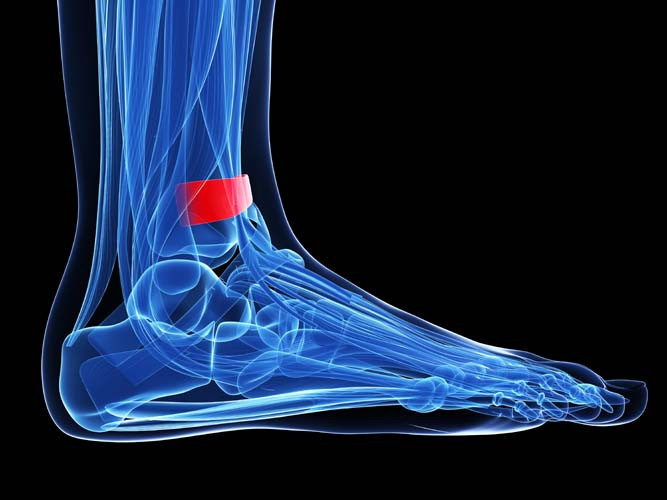

Başparmağın eğilmesi ile beraber ayağın mekaniğinin bozulmaya başlaması da Halluks Valgus’un diğer bir belirtisi olmaktadır. Normalde başparmağın altında olması gereken nasır, başparmak havaya kalktığı için ikinci ve üçüncü parmağın altında oluşmaya başlamaktadır. Bu durum ayağın yük taşıma şeklinin değişerek mekaniğinin bozulmasına ve yürüme sırasında ayak ortasında da ağrı oluşmasına sebebiyet vermektedir.

Hastalığın daha ileri aşamalarında ayak başparmağı ikinci parmağın altına girmeye başlamaktadır. Başparmak, ikinci parmağı da alttan yukarı doğru ittiği için ileri evre hastalarda ikinci parmağın altında ve üstünde nasırlar oluşmaktadır. Ayakkabıya sürtünme fazla olursa çok sık olmamakla birlikte yara ve iltihaplanma da görülebilir.